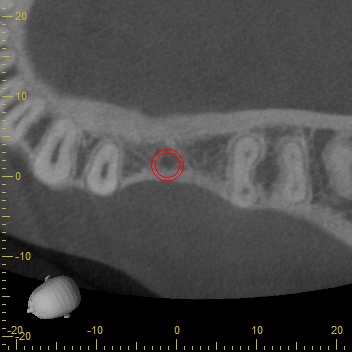

CTスキャンによるシュミレーション

永久歯がもともとないところは骨のボリュームが足りないことがほとんどです。

今回もCTスキャンで調べるとインプラントの外側に骨が足りないことが分かりました。足りない量がそれほど多くなかったためにインプラント埋め込みと同時に骨補填材を移植して骨造成をすることになりました。